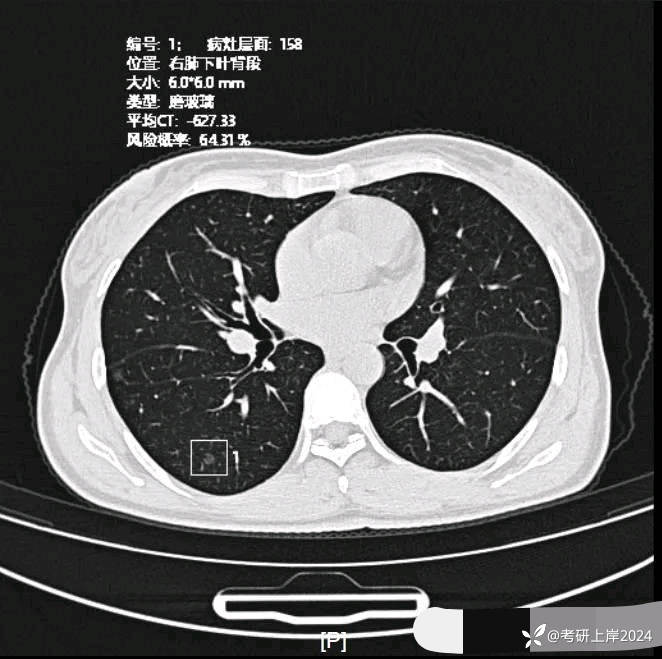

患者最近的检查有AI辅助诊断意见,找出的病灶分别如下:

病灶1:右上叶长径8毫米纯磨玻璃结节,边上有微小血管贴着,整体轮廓较清,怕哪样欠均匀。考虑不典型增生或原位癌可能性大;

病灶20:右下叶磨玻璃结节,轮廓清楚,有微小血管进入,瘤肺边界清。考虑原位癌或不典型增生可能性大;

病灶21:右下叶磨玻璃结节,轮廓清,考虑不典型增生可能性较大;

病灶24:右下叶叶裂处结节,实性,边缘光滑,没有收缩力,密度过高,考虑肺内淋巴结或碳沫沉积可能性大。2023年12月最明显的结节形态:

与2024年3月份复查时的对比,几乎没有变化。我的回复:两肺多达20几处结节,除了最后一处实性的考虑良性的,其他的都是磨玻璃密度,整体轮廓较清的,这在3月份的AI诊断上都有截图,其中最主要的几处就是我另外再截图了发来的这几处。它们也仍算是磨玻璃密度,病理大概会是原位癌可能性大,个把最坏可能是微浸润性腺癌,其实说不上明显实性成分,只是右上叶的那三处,最靠纵隔的那枚有血管穿过,显得像是混合密度,但肿瘤的成分仍是磨玻璃的。鉴于多发,又无法都通过手术全部切除,我的想法仍是再观察随访为主,待主病灶进展到有风险了再来考虑干预处理主病灶,并到时候兼顾同侧的其他结节是否顺带解决一部分。目前先随访,意见供参考!感悟:今天为什么要分享其实挺常见的这种多发磨玻璃病例?我想主要是由于结友问诊了这么多医生,仍在继续问,说明她虽然这些结节目前风险不大,但对她的心理造成了很大的压力,这也是结友最常见的心理状态。我觉得心理的崩溃或不断钻牛角尖的思考或许在短期内导致的害处更甚于结节本身!她问了这么多医生,肯定大部分都认为能随访,目前也没有风险大到定得赶紧处理的病灶,但她仍在不停的问诊,总想得到更让其踏实的答案。但哪位医生能说这些不是恶性范围的呢?谁能告诉她这是正常的呢?那不可能呀!已对查出多发结节,致病因素不明、预防措施没有、切又切不光、用药也不用!你说除了正确认识它、理性面对它,你能如何?在问诊中,总是有结友问到底有没有增长1毫米?CT值有没有增加?血管有没有进入?空泡有没有?实性成分有没有以及占多少?这些作为患者自己定要去纠结有何益?能说明什么问题呢?总体上,如果像今天这位结友医院提供AI辅助诊断意见,那是大小、体积、CT值、风险程度都会列的清清楚楚。但实际上在临床工作中,医生并不必这样按数值去判断风险或决定是否手术,如果这样还需要医生干嘛,AI全部会给出意见,AI说该开刀的转给胸外科、AI说可随访的回家下次来复查、AI说有风险的去消融等等。事实上我一直认为,我们看肺多发结节,关键就抓住:1、最主要的病灶风险如何:如果主病灶仍是危险性不高能随访,那么既无必要去数一共是10处还是15处,抑或20处,都没有意义,因为反正是按时复查就行;2、不同时期影像的对比,过于细微的差别,当其不足以改变临床决策的时候,就失去了深究的意义:纯磨只需随访的,你是5毫米也好,7毫米也罢,有何相干?反正仍不需干预处理。实性结节怕它危险,但若2毫米、3毫米,连影像特征都看不明白,更不可能为了这类结节去切下来化验,那么总在担心到底良性还是恶性,会不会是小细胞癌有何用?所以我在临床工作中,基本上不在意具体大小,也不去测CT值,关注一是实性成分有没有;二是血管有没有进入以及异常增粗;三是对比最早的与最近的有没有明显变化。放平心态、理性面对,该随访时按时随访,该干预时下决心干预!